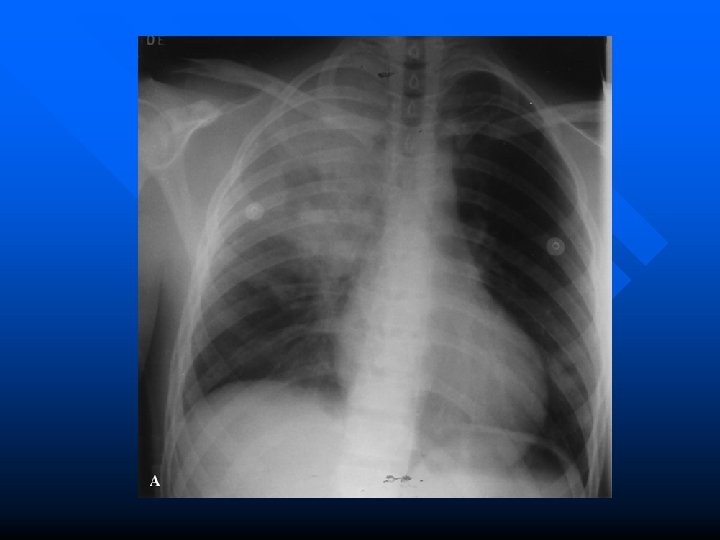

“Stick-em up!” 41 year old male, “minding his own business, ” single GSW to R chest by small caliber handgun. Tachycardic. BP 90/50. Decreased BS to R chest. CXR opacification of R lung. CT on R initial drainage 1000 cc. – Does this patient require immediate OR?

Hemothorax • • • Accumulation of blood in pleural space Can cause severe hypovolemia, shock, and decrease vital capacity Generally due to injured lung parenchyma – usually self-limiting More severe bleeding from intercostal and internal mammary arteries Uncommonly from great vessels

Xray in Hemothorax n n n Poor ability to predicit amount of blood in chest cavity using CXR 250 ml required to cause blunting of costophrenic angle on upright On supine film fluid layers posteriorly – increased density over hemithorax n 25 % of cases associated with pneumothorax – may see air fluid level on upright CXR n CT more sensitive than CXR but generally clinically insignificant if not visible on CXR

Treatment #38 chest tube at midaxillary line n BIG PROBLEM = BIG CUT = BIG TUBE n

Who needs the OR? n n n initial drainage > 20 ml/kg of blood (1500 ml) persistent bleeding at > 7 ml/kg/hr (500 ml/h) increasing hemothorax on CXR persistent hypotension despite adequate blood replacement and other sites ruled out as source patient decompensates after initial resuscitation 15 mg/kg of blood initially or 3 -4 mg/kg/h